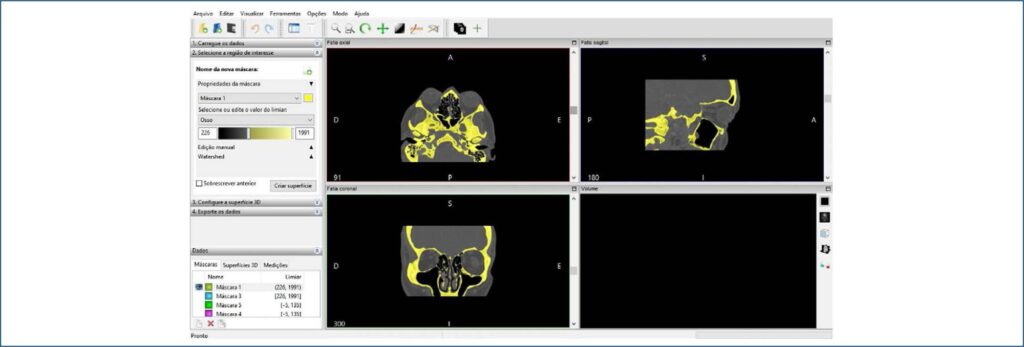

Propor um protocolo para a criação de arquivos digitais a partir de imagens de tomografia computadorizada a serem impressas em 3-D e usadas como modelo de material didático oftalmológico usando software de código aberto, InVesalius®, Bender® e Repetier-Host©.

Foram utilizadas imagens em formato DICOM provenientes de dois exames de tomografia computadorizada de órbitas para a impressão tridimensional. Para manuseio das imagens, foram utilizados o InVesalius®, versão 3.1.1, para delimitar e limpar a estrutura de interesse e também para converter em formato STL. O Blender®, versão 2.80 foi usado para refinamento. A imagem em STL foi então enviada para o programa Repetier-Host, versão 2.1.3, que divide a imagem em camadas e gera as instruções para impressão da peça em ácido polilático na impressora tridimensional.